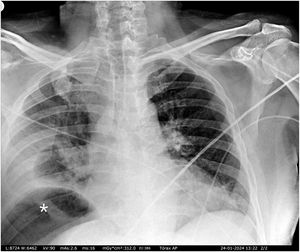

Varón de 49 años, sin antecedentes salvo por una tumorectomía renal derecha laparoscópica realizada hace un mes, por quiste Bosniak III-IV. Se presenta en urgencias con malestar general, dolor abdominal inespecífico y disnea. Se realiza inicialmente una radiografía de tórax (fig. 1), la cual es sugestiva de neumoperitoneo, seguida de un TAC abdominal (fig. 2) que muestra una colección subfrénica con nivel hidroaéreo. Durante la intervención quirúrgica se confirma una perforación de colon derecho retroperitoneal. Aunque las perforaciones de colon retroperitoneal suelen acompañarse de retroneumoperitoneo y abscesos retroperitoneales, en este caso no se identifican ninguna de las dos circunstancias, presentando únicamente un absceso subfrénico con nivel hidroaéreo, la cual, además, nos proporciona una falsa imagen de neumoperitoneo en la radiografía de tórax.